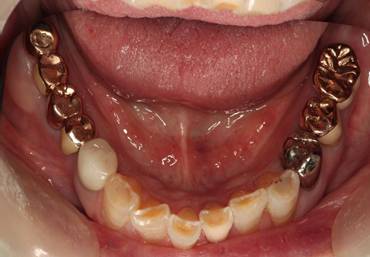

術前。すべての歯が歯周病の末期状態でブリッジ全体がうごいて噛めないとの訴え。右上の犬歯が腫れていました

固定式のブリッジが入っていましたが歯周病で動いています

下顎前歯部には歯石の沈着がみられます